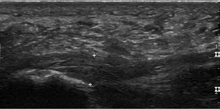

Plantar fasciitis is usually diagnosed by a health care provider after consideration of a person's presenting history, risk factors, and clinical examination.[2][14][15] Tenderness to palpation along the inner aspect of the heel bone on the sole of the foot may be elicited during the physical examination.[2][10] The foot may have limited dorsiflexion due to tightness of the calf muscles or the Achilles tendon.[7] Dorsiflexion of the foot may elicit the pain due to stretching of the plantar fascia with this motion.[2][11] Diagnostic imaging studies are not usually needed to diagnose plantar fasciitis.[7] However, in certain cases a physician may decide imaging studies (such as X-rays, diagnostic ultrasound or MRI) are warranted to rule out serious causes of foot pain.

Normally the plantar fascia has three fascicles with the central fascicle thickest at 4 mm, the lateral fascicle at 2 mm and the medial at less than a millimeter in thickness.[16] In theory, the likeliness of fasciitis increases with increasing thickness of plantar fascia at the calcaneal insertion, with thickness of more than 4.5 mm being somewhat useful on ultrasound and 4 mm on MRI.[17] Findings on imaging such as plantar aponeurosis thickening, however, may be absent in symptomatic individuals or present in asymptomatic individuals thereby limiting the utility of such observations.[12]